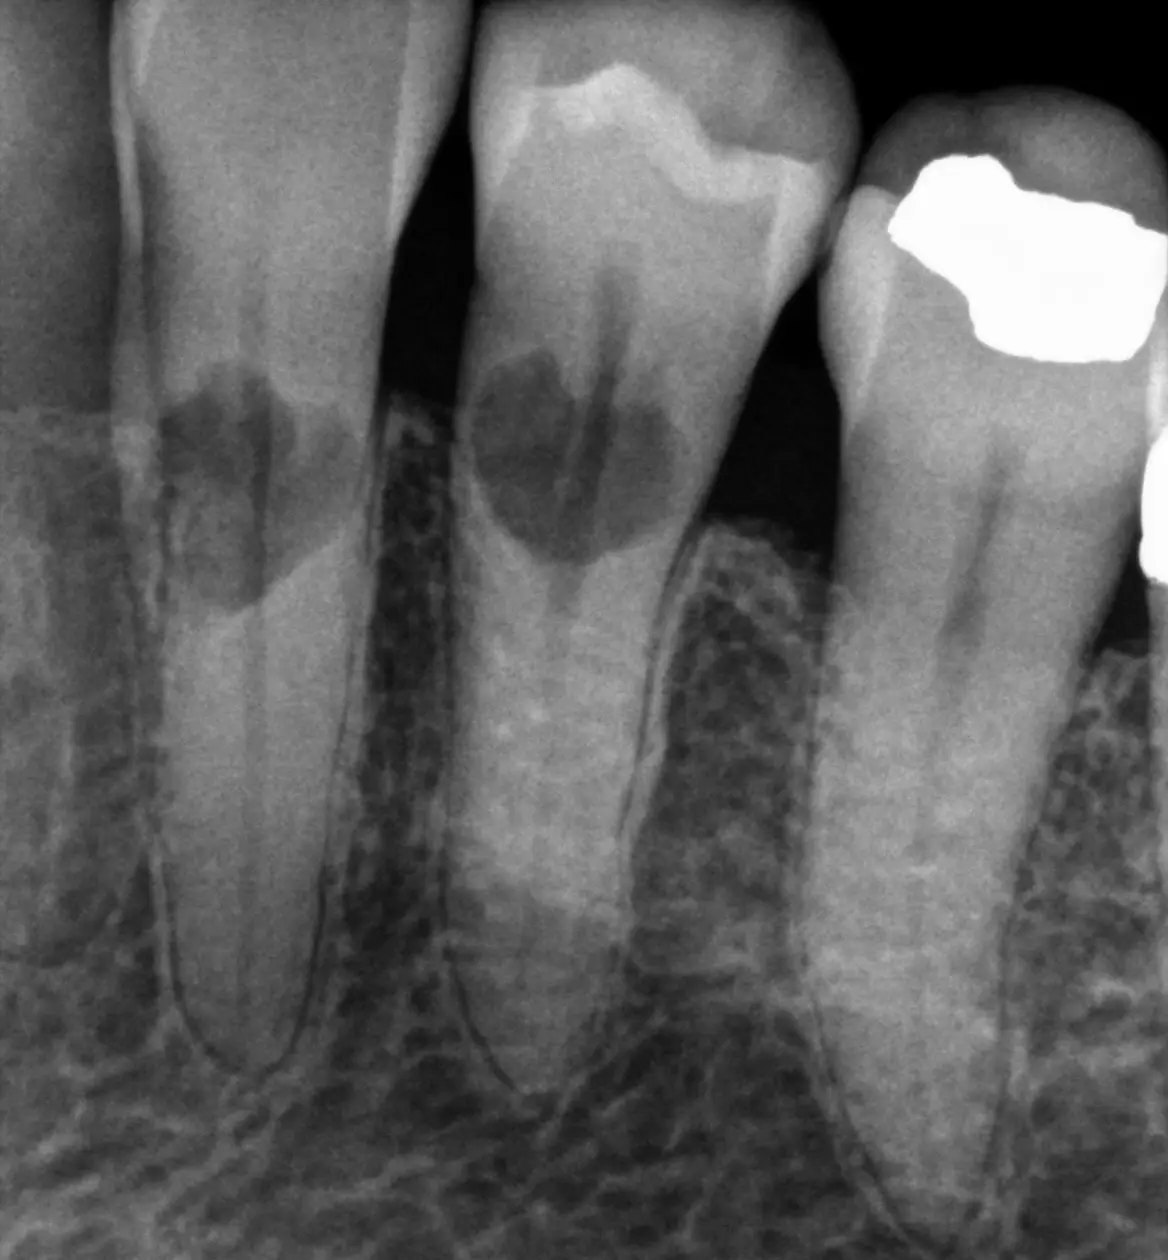

Resorption

Resorption is a condition where the tooth’s structure starts to break down, either from the inside out or from the outside in. It can be caused by trauma, inflammation, or other factors. Endodontic treatment for resorption involves removing the damaged tissue and reinforcing the tooth with materials that help prevent further damage. The aim is to save the tooth and maintain its functionality as much as possible.